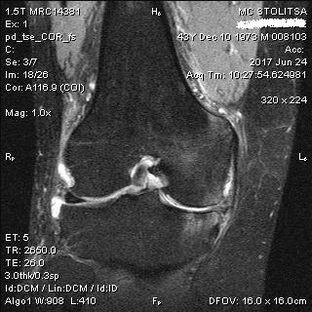

Ceļa locītavas osteoartrīts uz MRI